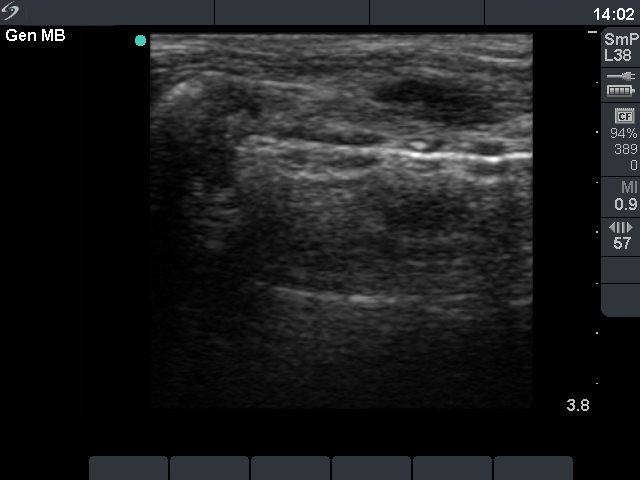

At the time of the discontinuation of steroid therapy (third row):

The size of the lesion was 15x8x19 mm (width x depth x length).

2 months later (fourth row) :

The size of the lesion decreased further and was 10x6x12 mm (width x depth x length).